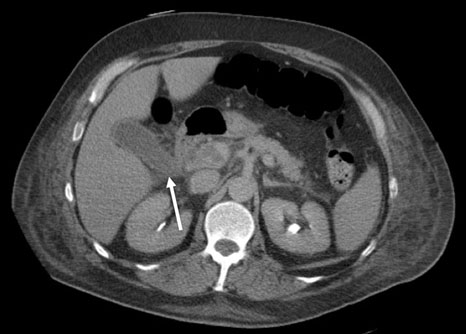

A pelvic ultrasound was done which revealed a possibility of a bicornuate uterus and a 4.4 cm mass seen within left ovary which is hypoechoic in nature which probably represent endometrioma (Figure 1). There was no free fluid noted or any adnexa mass seen. The appendix was not visualized. Due to her nonresolving abdominal pain, a CT scan of abdomen and pelvis was done. It was noted on the scan that there was an inflammatory change in the distal ileum with the appendix being slightly dilated at 6.3 mm and could suggest an early appendicitis (Figure 2 and Figure 3). Apart from the left ovary cyst there were no other abnormalities noted.

Figure 2: Axial CT scan: red arrow indicates the slightly dilated appendix at 6.3 cm with inflammatory changes in the distal ileum.